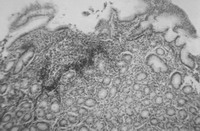

Լորձաթաղանթի հիմնաթիթեղում նկատվում էին տարբեր մեծության գեղձային տարրեր, լիմֆոհիստոցիտային ծծանցումներ, այտուց, էպիթելի թեփոտում (նկ. 2), իսկ ծածկող փոսիկային էպիթելում, հավելյալ բջիջների բջջապլազմայում և ստամոքսի փոսիկների լուսանցքում՝ չեզոք պոլիսախարիդներ։

Նկ. 2. Ստամոքսի խորշային հատվածի լորձաթաղանթի սուր բորբոքում թեփոտմամբ։ Հեմատոքսիլին – Էոզին, X 400